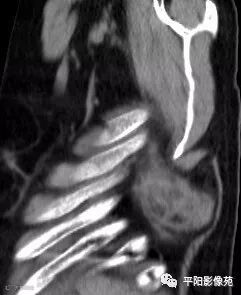

影像表现

两例患者均为左侧肩胛下实性软组织肿块,边缘模糊,质软,内为肌肉样密度及脂肪密度,以肌肉样密度为主。

CT:边界模糊,与肌肉相似的密度,病变内部可见点状、条状脂肪密度,增强扫描轻度强化或无强化。